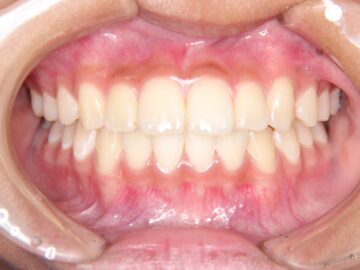

治療後

八重歯・歯がガタガタしている